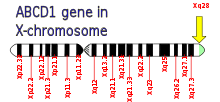

ALD is caused by mutations in ABCD1, located at Xq28 and demonstrates X-linked recessive inheritance. The gene ABCD1 encodes a peroxisomal membrane transporter which is responsible for transporting very long chain fatty acid substrate into the peroxisomes for degradation.[5] Mutations in this gene that interfere with this process cause this syndrome.